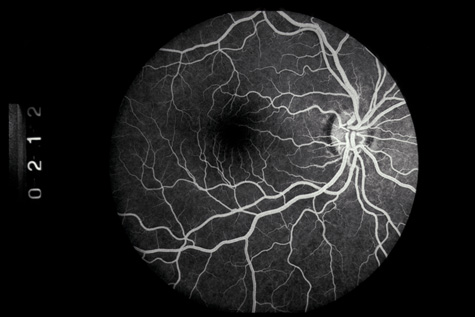

Similar to many conditions that damage Bruch's membrane, choroidal ruptures can, months to years later, be complicated by development of a choroidal neovascular membrane, with serous or hemorrhagic retinal detachment and loss of central vision (Fig. 23).87–89 They usually respond well to laser therapy. Also, studies have demonstrated that subfoveal choroidal neovascular membranes from etiologies other than age-related macular degeneration can benefit from photodynamic therapy.90,91

Fig. 23. A: Choroidal neovascular membrane originating from an old choroidal rupture. B: Fluorescein angiography confirms the diagnosis.